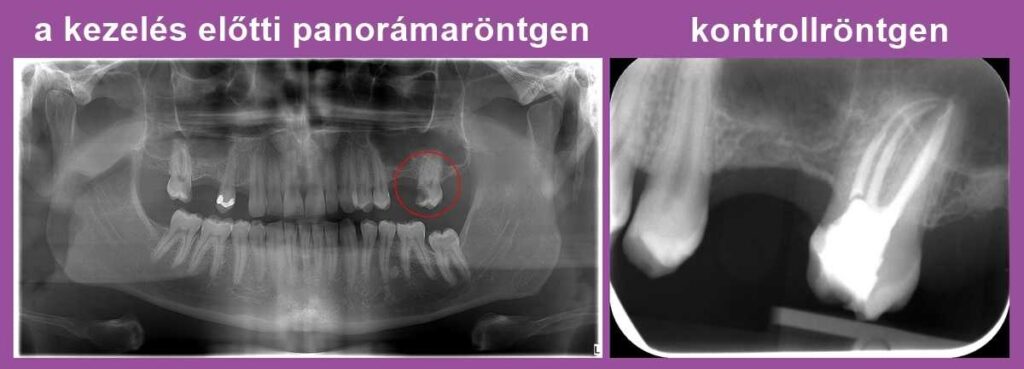

Dr. Molnár Katalin páciense arra panaszkodott, hogy foga érzékeny a hidegre és a melegre. Az első képen, a panorámafelvételen bekarikáztuk a fájdalmat kiváltó bal felső hetes fogat. Egy mély szuvasodás látható rajta, amely nagy kiterjedésű foganyag-veszteséget okozott. Nyilvánvalóvá vált, hogy az érzékenység hátterében ez a károsodás áll.

A kontroll röntgenfelvételen jól kivehető, hogy a fognak elöl nem egy, hanem két gyökere van: ha ezt nem sikerül megtalálnunk és letömnünk, az később panaszokat és gócos tüneteket okozhat.